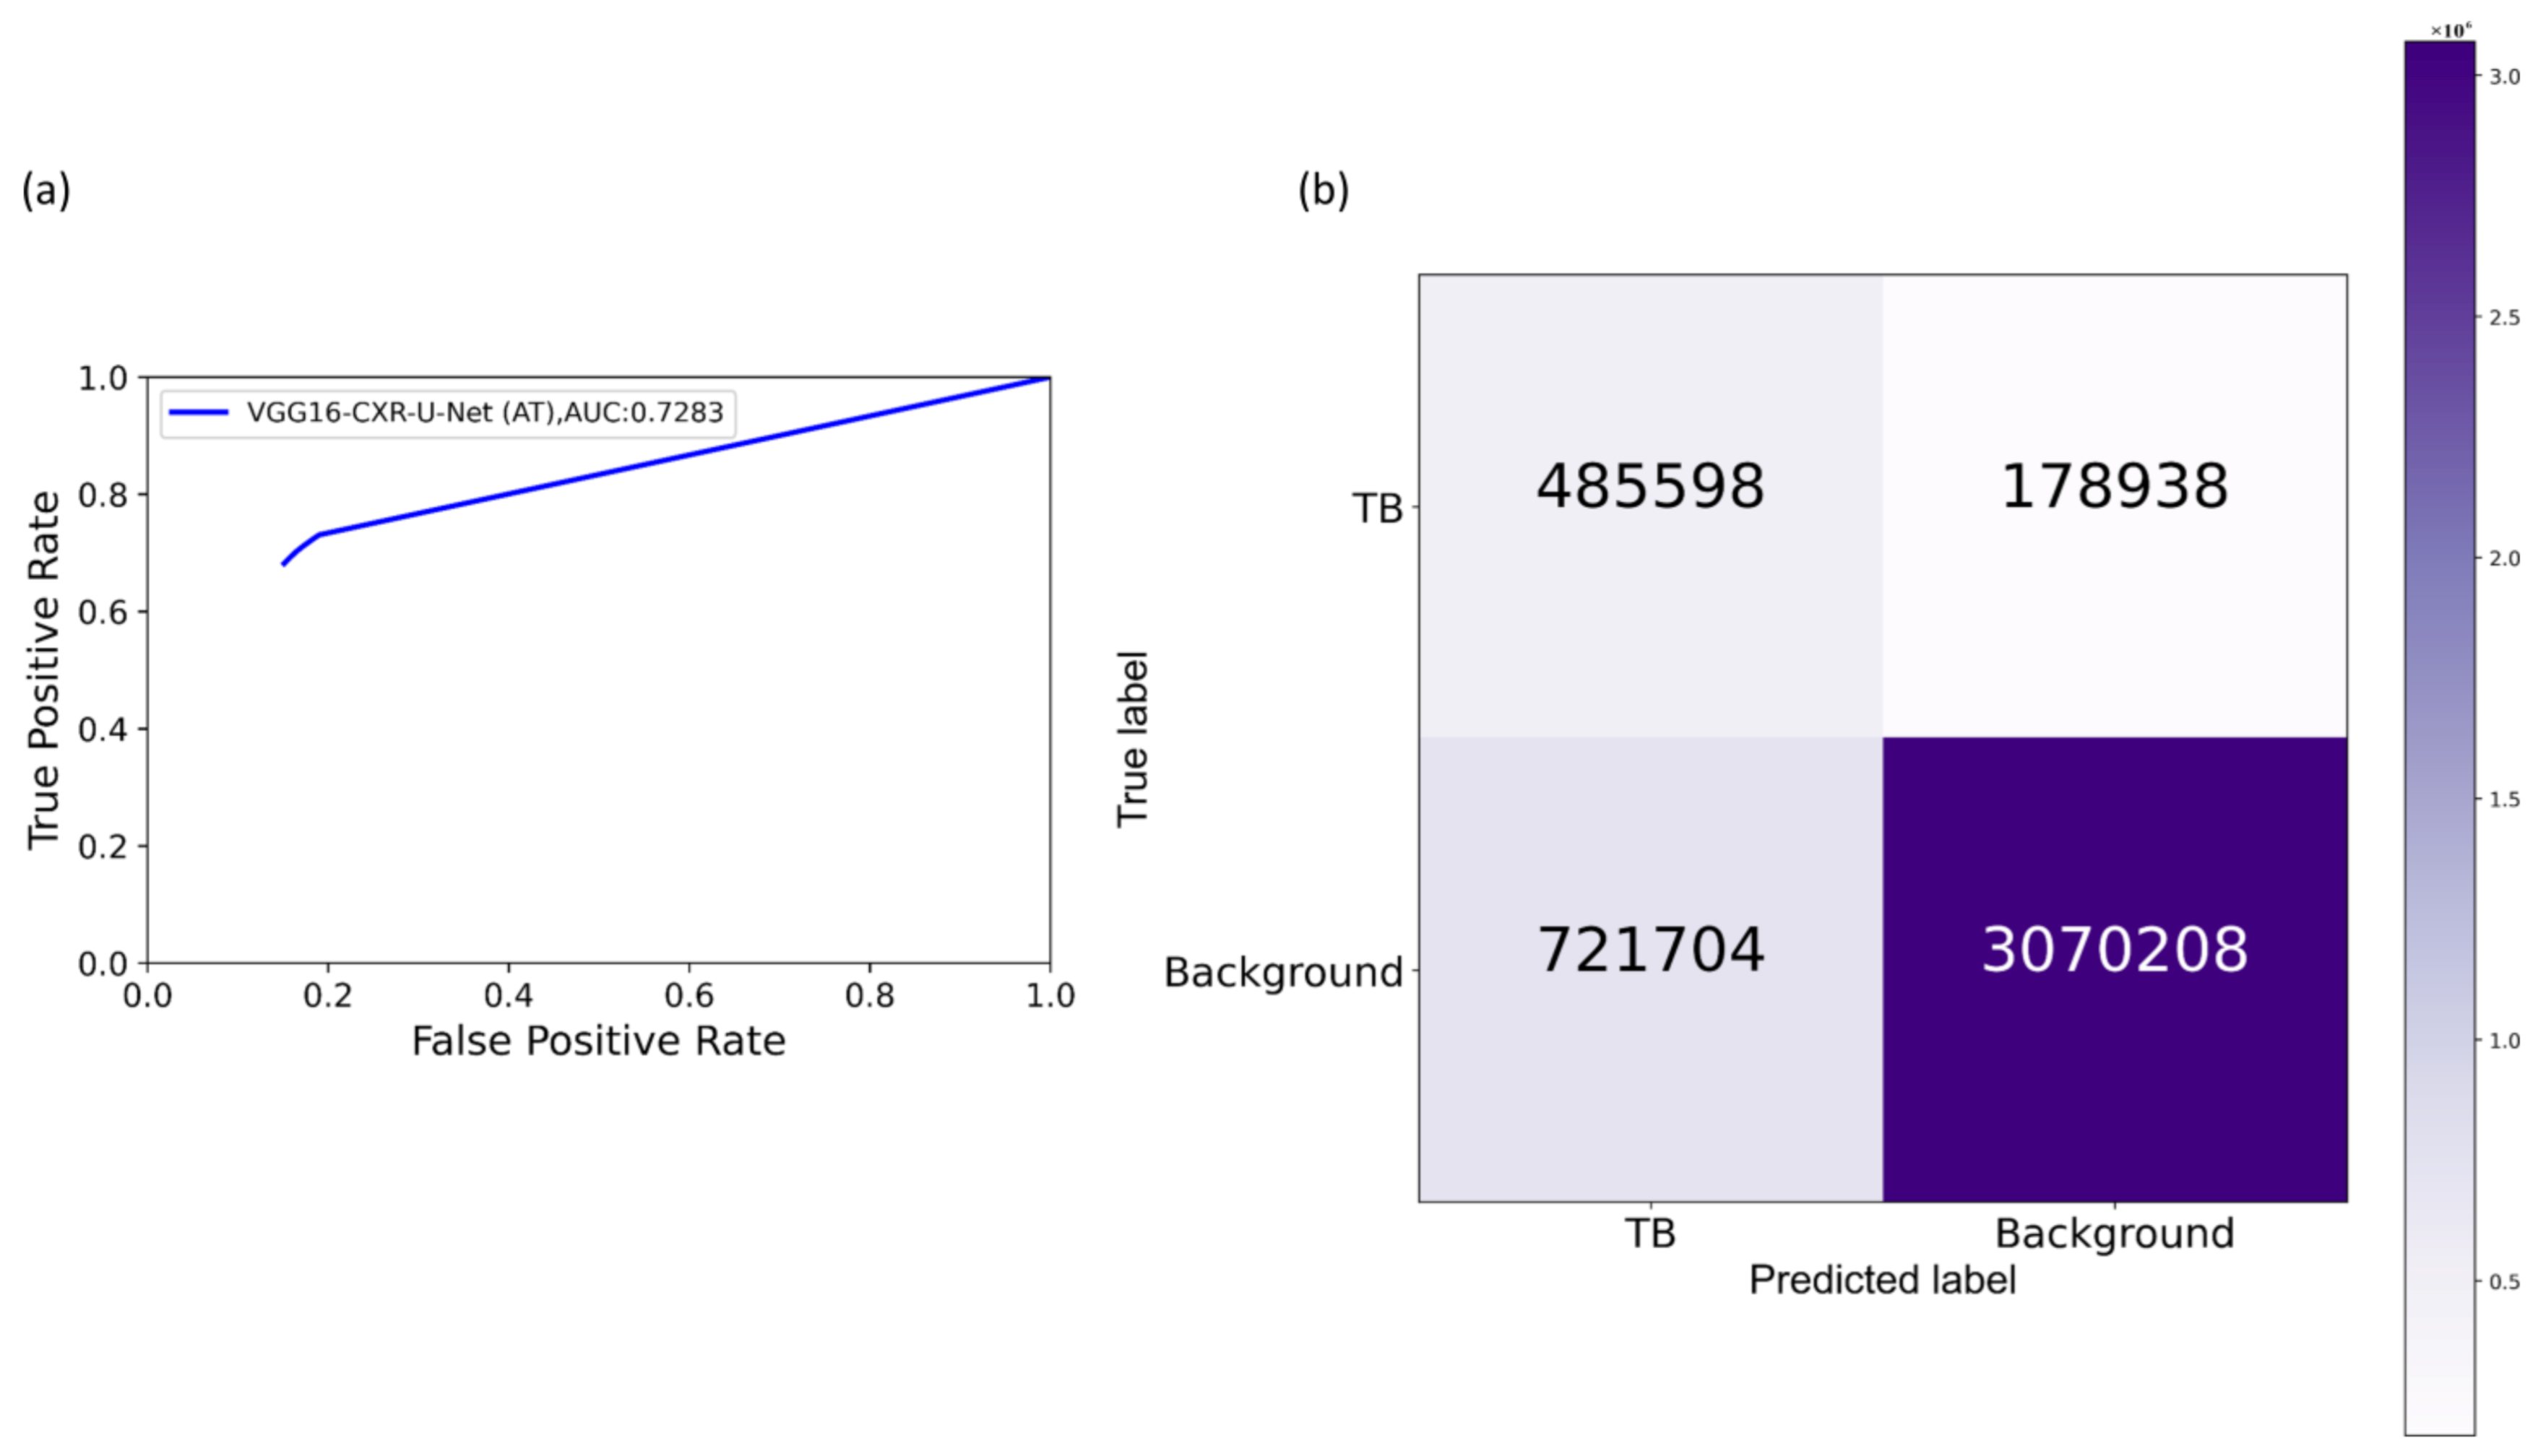

Section 2.4 to segment the lungs in this collection. Following lung segmentation, we rescaled the disease bounding box coordinates and converted them into binary masks. Recall that since we are using bounding boxes for training, a fraction of the pixels within these are false-positive (FP) training labels, which adversely impact our outcome. These masks and their associated CXRs are used to train and test the models. We used a fixed seed value to allocate 10% of the training data toward validation. Variability is introduced into the training process by augmenting the training data through affine transformations, including horizontal flipping, height and width shifting, and rotations. Callbacks are used to store model checkpoints, and the best performing model is used to segment TB-consistent ROI.

We further evaluated the performance of the U-Net models with cross-institutional test sets. The Shenzhen TB CXR-Subset-2 (n = 68) and the Montgomery TB CXR (n = 58) collections are individually used as test sets toward this evaluation. Such cross-institutional testing would demonstrate the generalization ability of the models and their suitability for real-time deployment because the test set is diverse and unseen during the training process.

2.8. Selecting Appropriate Loss Function and Other Evaluation Metrics

U-Net models, though having an excellent potential toward accurate medical image segmentation, often suffer from data imbalance. These issues are particularly prominent in applications that involve lung/TB-consistent ROI segmentation, where the number of lung/TB-consistent ROI pixels is markedly lower compared to the total image pixels. Such imbalanced training may lead to learning bias and may adversely impact segmentation performance. To alleviate issues due to these data imbalances, a generalized loss metric based on the Tversky index has been proposed [

Here a and b denote the set of predicted and GT binary labels, respectively, a0k is the probability of the pixel k to belong to the lung/TB-consistent ROI, a1k is the probability of the pixel k to belong to the background, b0k takes the value of 1 for a lung/TB-consistent ROI pixel and 0 for the background and vice versa for b1k. Through empirical evaluations, we observed that the values for the hyperparameters α = 0.3 and β = 0.7 demonstrated a good balance between precision and sensitivity and that higher values for β resulted in improved performance and generalization while using imbalanced data and helped to boost sensitivity. Accordingly, we used these hyperparameter values in the current study. We used callbacks to store model checkpoints after the completion of an epoch. The best of the stored checkpoints is used as the final model for the subsequent analysis.

We measured segmentation performance in terms of the following metrics: (i) confusion matrix; (ii) Jaccard index, otherwise known as the intersection of union (

Selecting the appropriate loss function: segmentation models often suffer from class imbalance issues, particularly in medical image segmentation tasks. This is due to the highly localized ROI, spanning for a very small percentage of the total number of image pixels. The issues with using the conventional BCE loss for such class imbalanced segmentation tasks are as follows: (i) the BCE loss weighs all image pixels equally; (ii) the model demonstrates low BCE loss and hence higher segmentation accuracy even if it misses all ROI pixels that spans a small portion of the total image. In this study, we used a customized loss based on Tversky Index, an asymmetric similarity measure that generalizes IOU and Dice metrics. The use of a customized Tversky index-based loss function with empirically determined hyperparameter values for the problem under study helped to improve segmentation performance by providing a finer level of segmentation control compared to using a conventional BCE-based loss. Computing a single precision and recall score at a specific IOU threshold does not sufficiently describe the models’ behavior. In this study, we used AP@[0.5:0.95] to effectively integrate the AUPRC by averaging the precision score at multiple IOU thresholds ranging from 0.5 to 0.95 (in 0.05 increments). Such a measure would help to better demonstrate models’ generalization ability and stability toward the segmentation task.